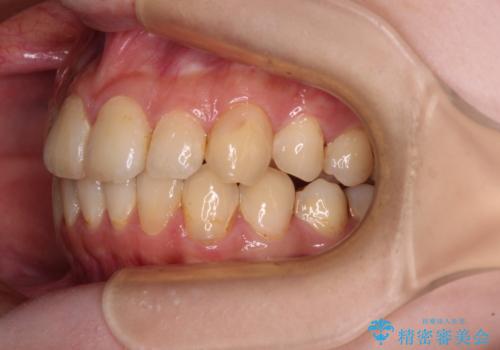

デコボコ歯列をきれいに インビザラインによる矯正治療

- 上下歯列全体のデコボコを気にして来院された患者様です。

主に下顎歯列全体の後方移動とIPR(歯と歯の間を削る)によってデコボコが解消するように設計し、インビザラインにより治療を行うこととしました。